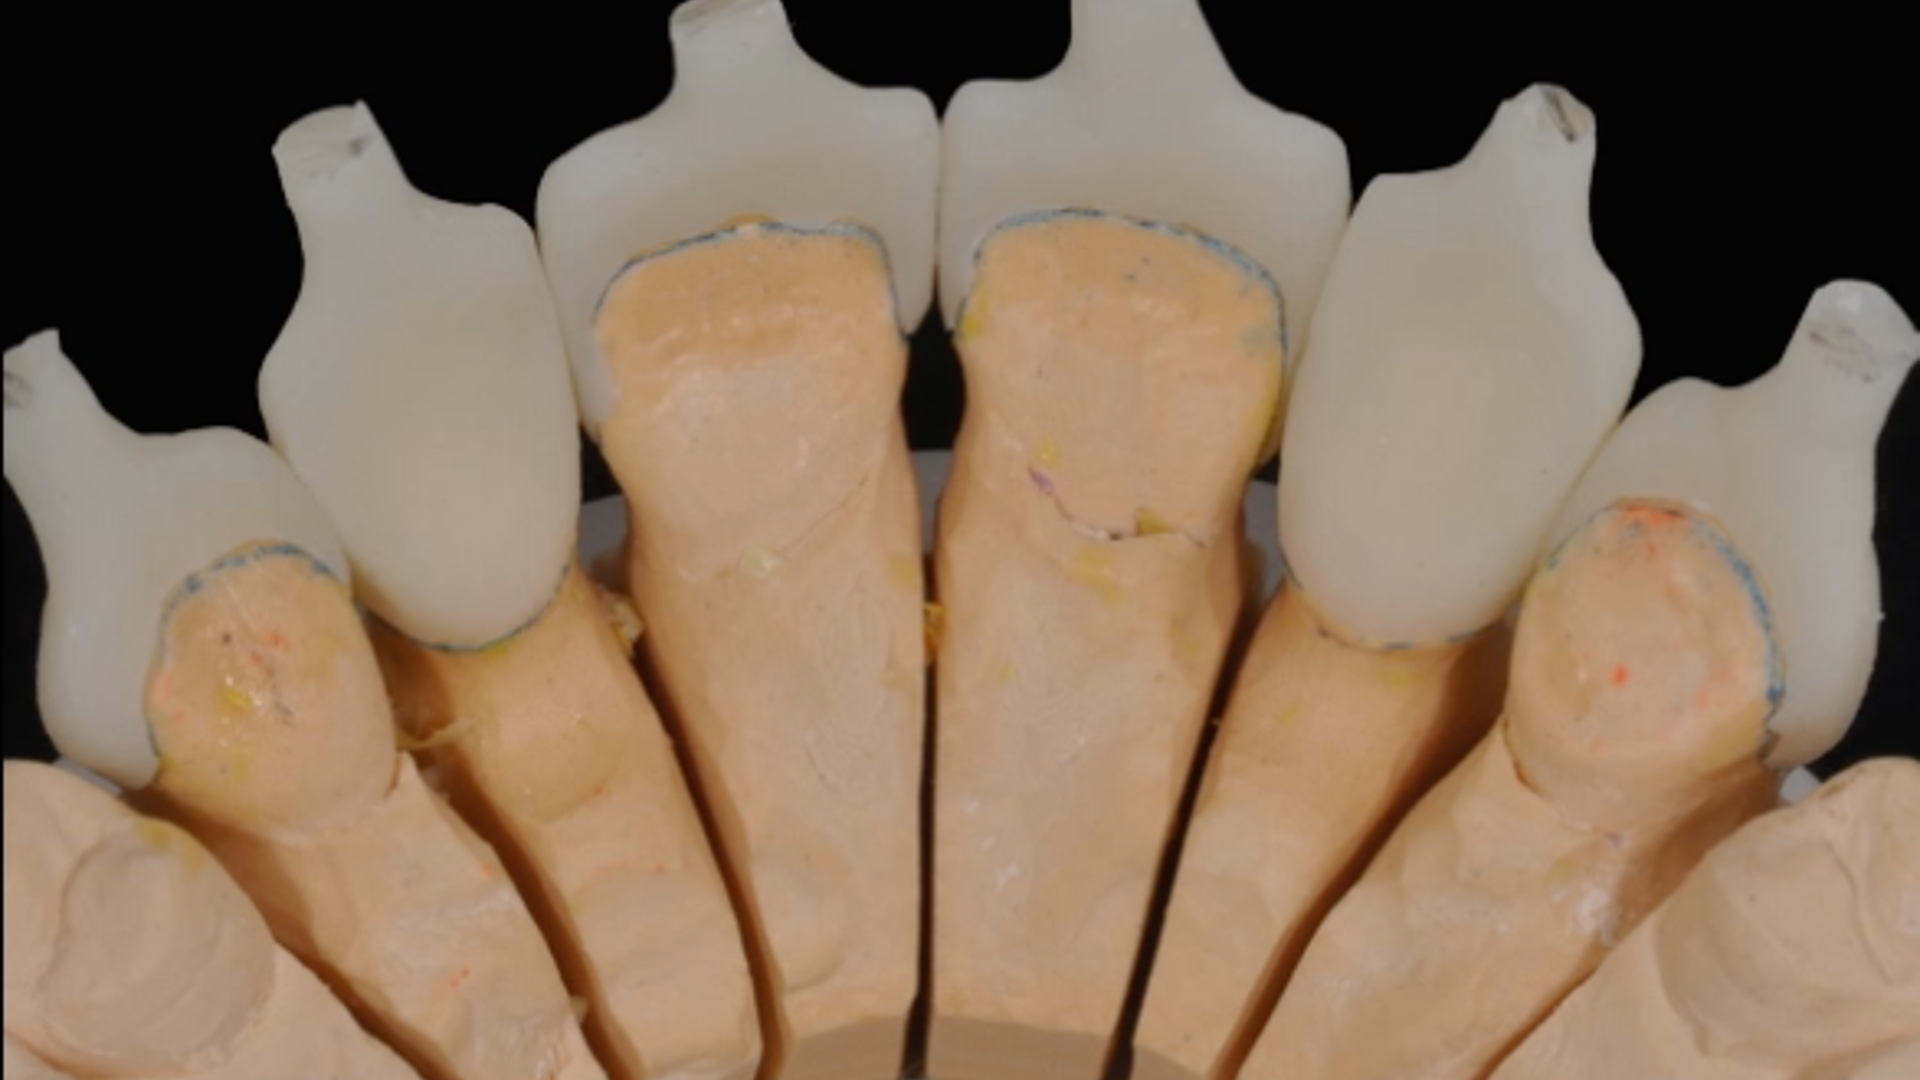

Clinical case - MIPP 1: conventional buccal veneers procedures

Clinical case - MIPP 3 (part 1 of 3): treatment planning and data collection

Clinical case - MIPP 3 (part 2 of 3): dental impression and provisional management

Clinical case - MIPP 3 (part 3 of 3): finalisation, restorations construction and cementation

MIPP 2: the new concept behind Full-Veneers to optimise aesthetics and functionality

MIPP 2B: clinical case of Full-Veneers in openbite with preserved enamel tooth structure

MIPP 2: MIPP 2A and MIPP 2B combined technique